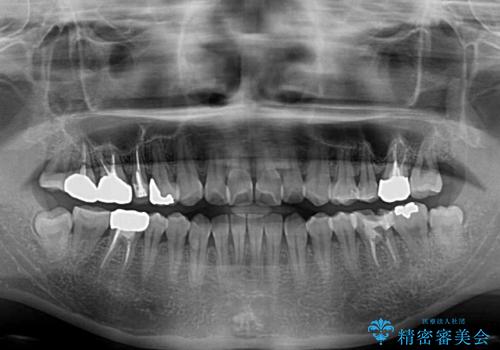

- 捻れた前歯と目立つ銀歯を気にして来院された患者様です。

歯列不正は軽微であったため、インビザライン・ライトにて改善することとしました。

左下大臼歯は根管治療が必要であったため、矯正治療前に根管治療を行い、その後矯正治療を行うこととしました。

矯正治療後には期にある銀歯を全てセラミッククラウンなどで補綴治療することとしました。